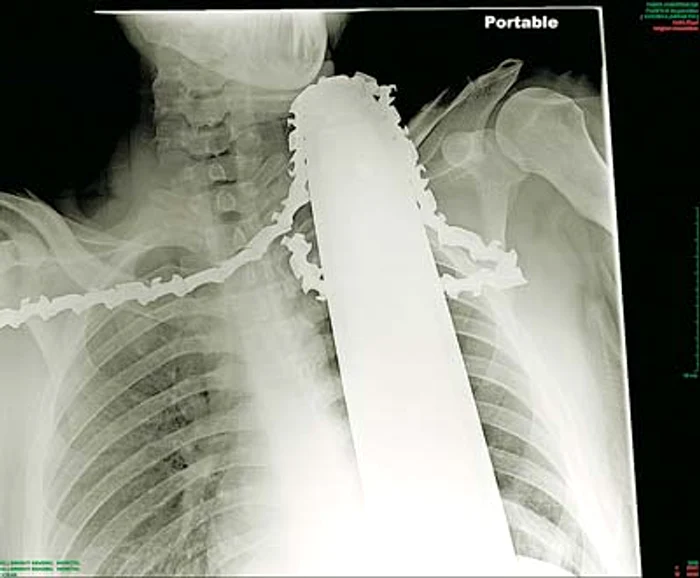

S-a născut a doua oară! James Valentine din Pennsylvania, Statele Unite, a păcălit moartea, după ce drujba cu care tundea copăceii din curtea casei i-a sărit direct în gât.

Tânărul de 21 de ani s-a urcat într-un copac, când la un moment dat, şi-a băgat din greşeală drujba în gât. Americanul a oprit motorul maşinăriei, iar sângele a început să-i tâşnească din gât. Ţipetele lui de durere se auzeau în tot cartierul şi vecinii au sărit imediat să-l coboare din copac.

Lama drujbei a ratat milimetric arterelemajore ale gâtului

Până la venirea ambulanţei, nimeni nu a scos aparatul de tăiat, pentru a nu-i agrava hemoragia.

A scăpat ca prin urechile acului! Norocul lui a fost că drujba nu-i atinsese nici o arteră principală sau coloana vertebrală. Bărbatul a fost operat de urgenţă, iar acum se află în afara oricărui pericol. Abia aşteaptă să se întoarcă acasă şi să termine de curăţat curtea.

James Valentine a scăpat ca prin miracol. Lama drujbei a ratat milimetric arterele subclavie (arterele majore ale gâtului, n.r.) şi a tăiat doar muşchii gâtului. Mai mult, victima a avut putere de spirit să-şi menţină lama nemişcată, pentru a nu-şi provoca leziuni grave sau chiar o sângerare care i-ar fi fost fatală.